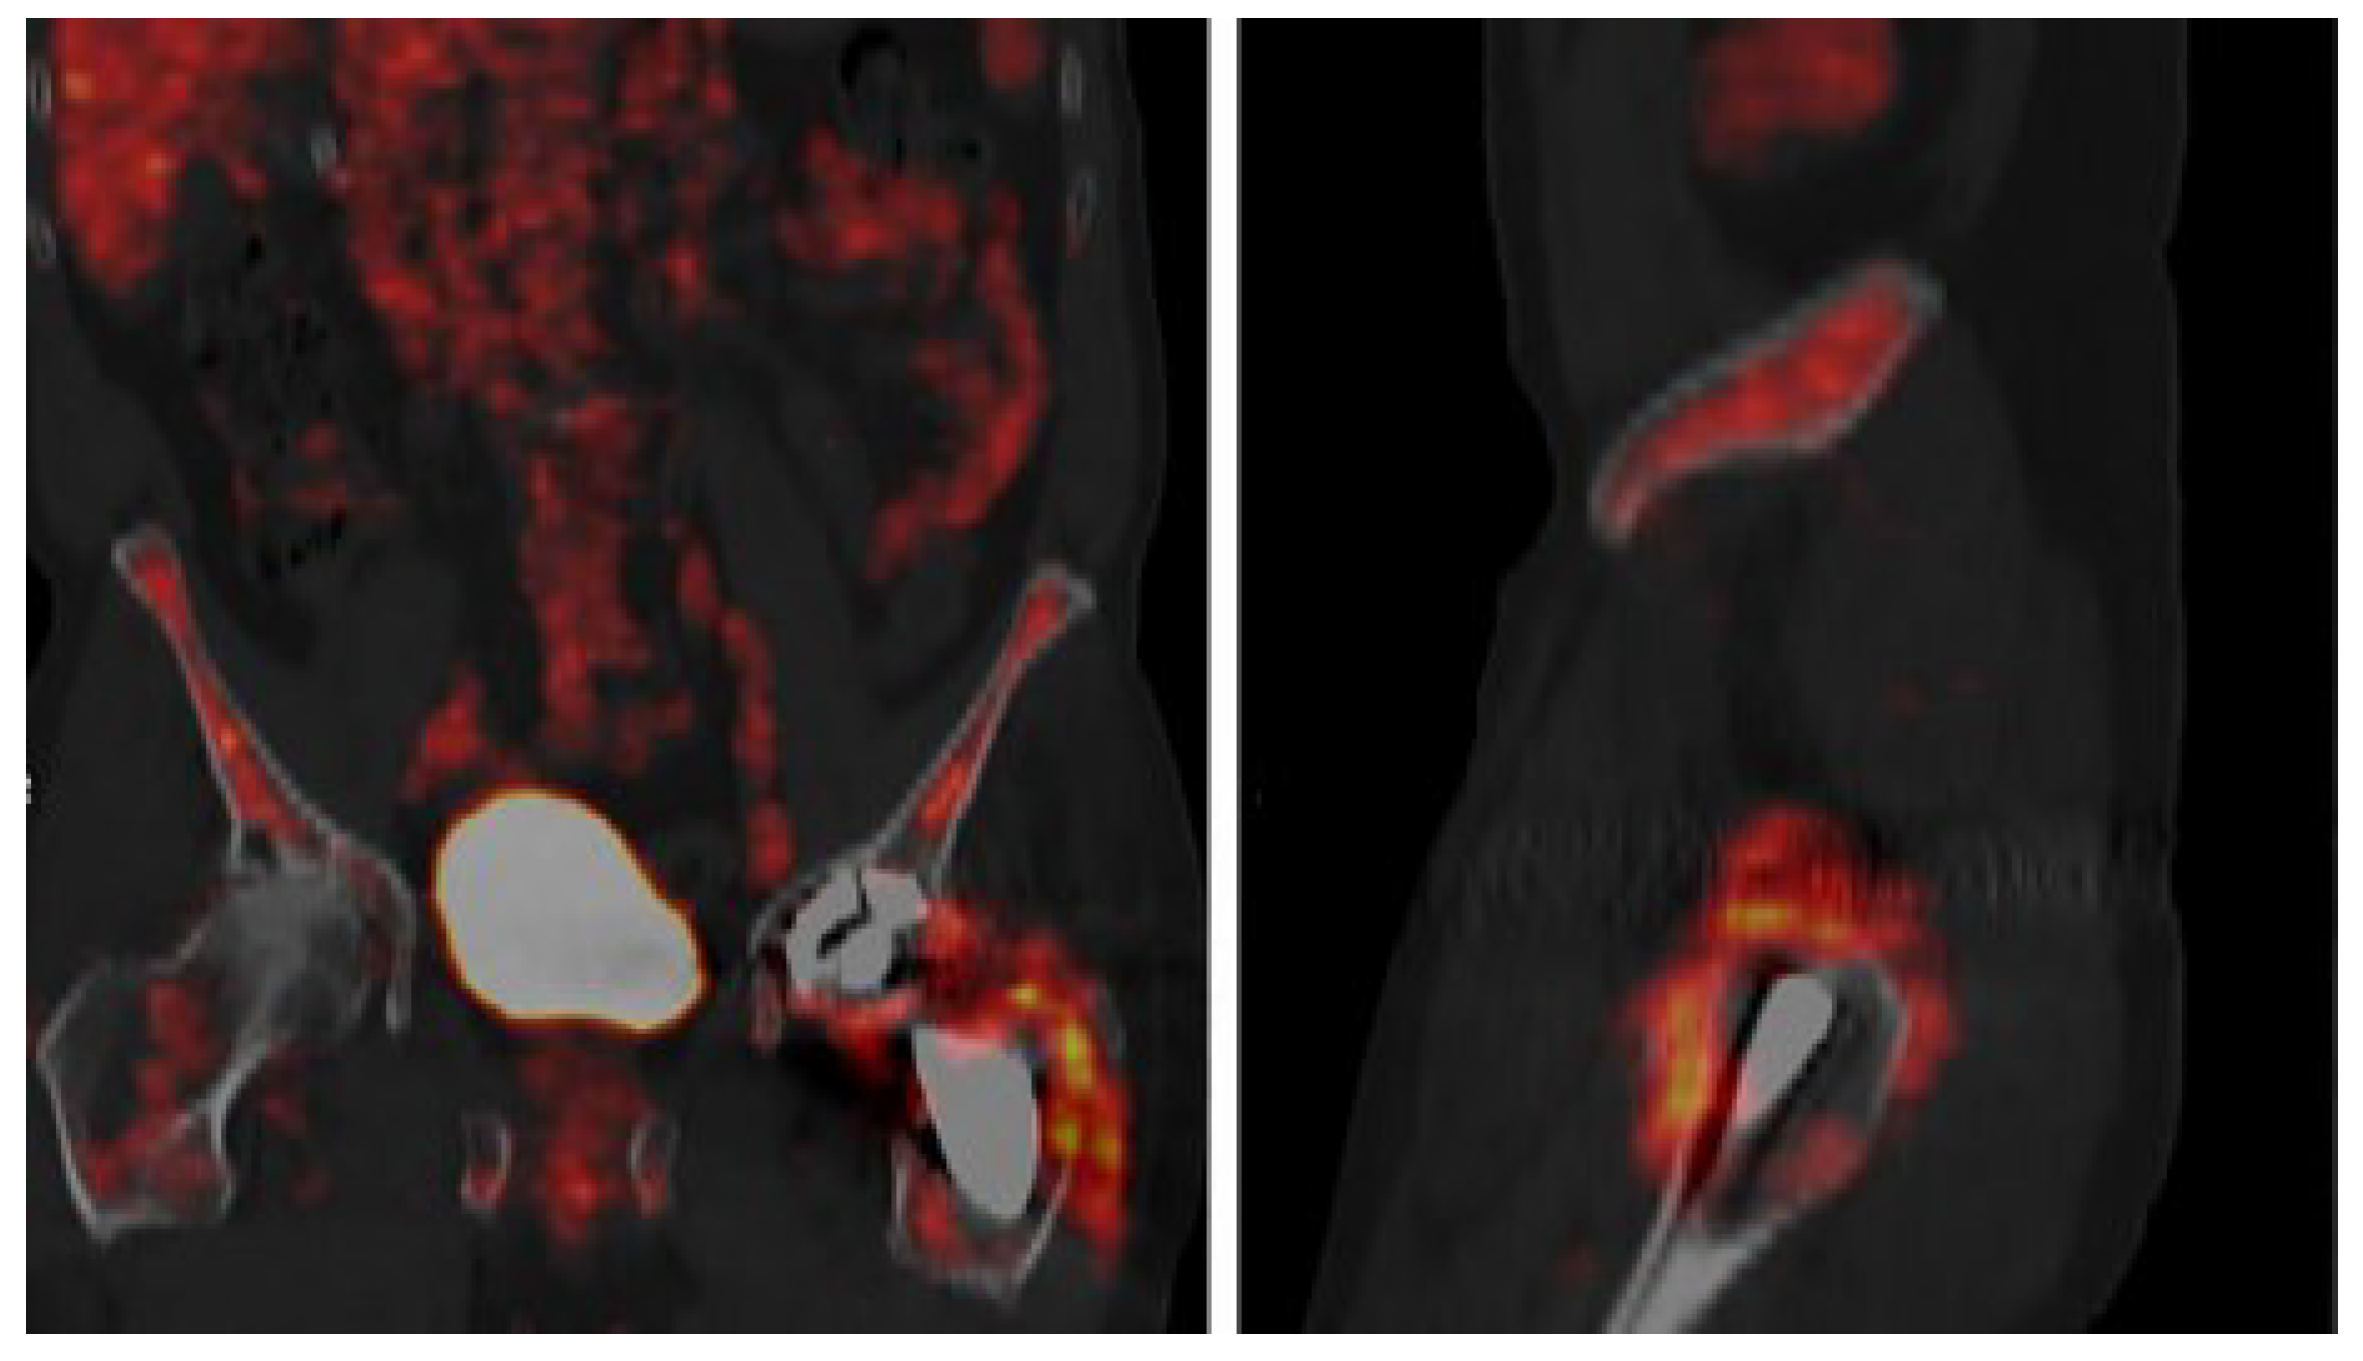

5.5. 18F-Fluorodeoxyglucose Positron Emission Tomography (FDG/PET/CT)